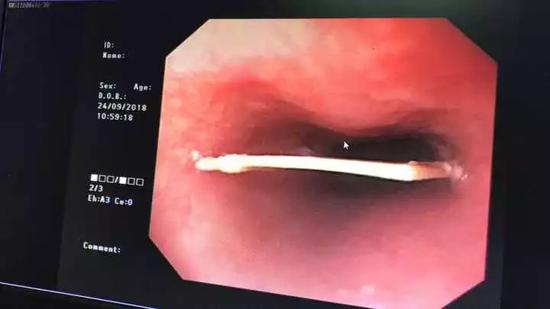

通過無痛胃鏡一看,小龍的食道里有個3厘米的鴨骨頭卡著,并且已有輕微劃傷出血,最后在醫護人員的努力下,骨頭被安全取出。

不過“這么大的一塊骨頭,我到底是怎么吃進去的呀!”看著從食道內取得的鴨骨頭,小龍始終不敢相信,后怕地說道:“以前我一直以為這種事只會發生在老人身上,沒想到,我這么年輕也會中招。”